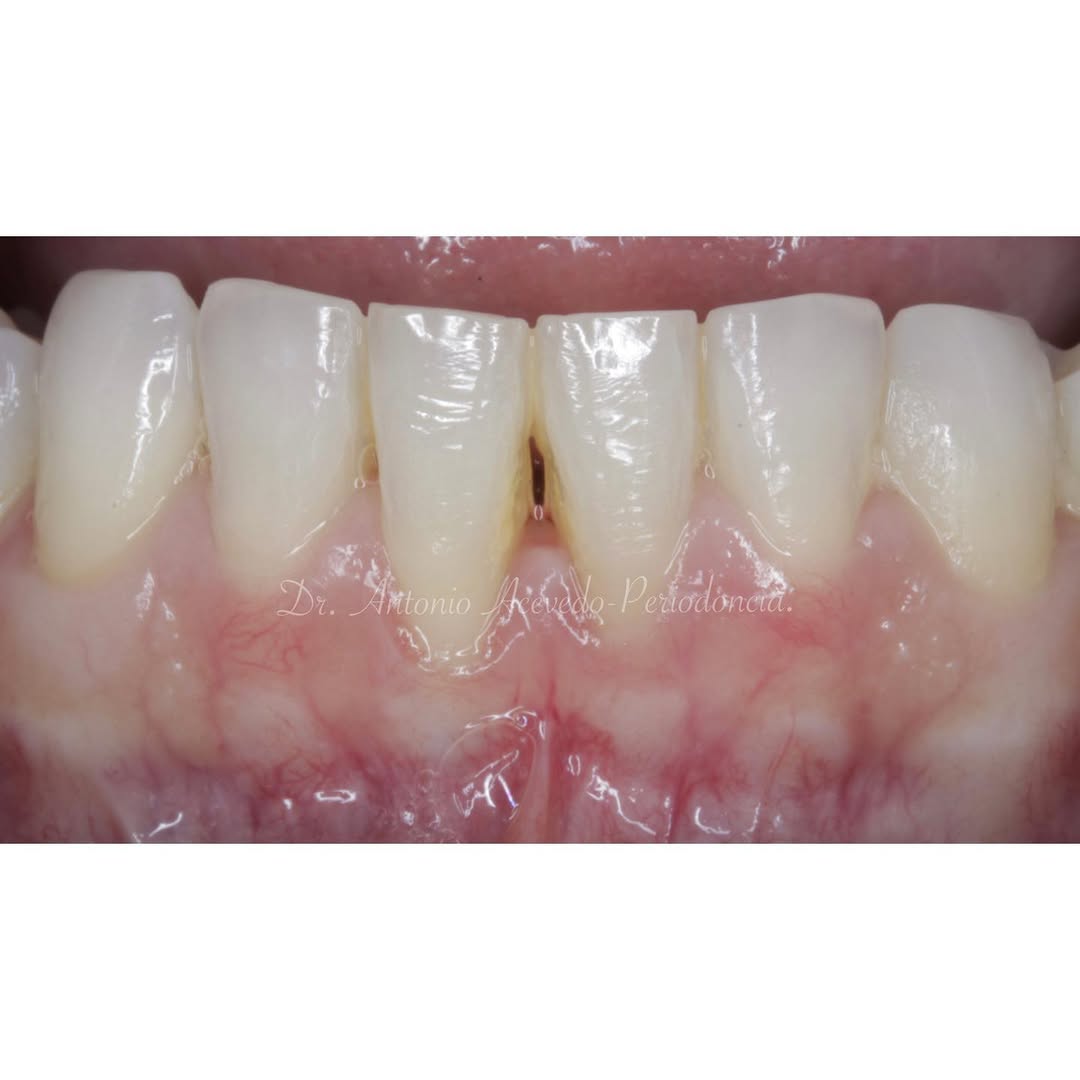

Se presenta un caso clínico de restauración directa en resina composite, ejemplo del valor de la precisión y la técnica meticulosa incluso en procedimientos considerados rutinarios dentro de la práctica diaria. El caso pone en evidencia la importancia del control de la morfología, la textura y la integración cromática, así como del adecuado aislamiento del campo operatorio y la estratificación del material, factores determinantes para conseguir un resultado natural, funcional y duradero. A través de una ejecución cuidadosa, se logró una restauración estéticamente imperceptible y funcionalmente estable, que respeta los principios de mínima invasión y adhesión efectiva. Este tipo de procedimientos, aunque cotidianos, reflejan la constancia y el nivel de exigencia clínica necesarios para ofrecer odontología de calidad en todos los casos, independientemente de su complejidad.